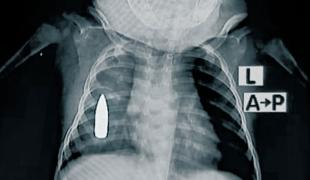

Les équipes de Médecins Sans Frontières mettent en œuvre un large éventail de soins : consultations, hospitalisations, interventions chirurgicales, soins psychologiques, soins médico-nutritionnels etc. dans des contextes d’urgence ou de difficultés d’accès aux soins.